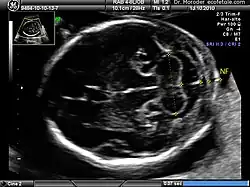

![]() Measurements of fetal nuchal translucency, nasal bone and facial angle according to the standards of the Fetal Medicine Foundation | |

A nuchal scan or nuchal translucency (NT) scan/procedure is a sonographic prenatal screening scan (ultrasound) to detect chromosomal abnormalities in a fetus, though altered extracellular matrix composition and limited lymphatic drainage can also be detected.[1]

Procedure

Nuchal scan (NT procedure) is performed between 11 and 14 weeks of gestation, because the accuracy is best in this period. The scan is obtained with the fetus in sagittal section and a neutral position of the fetal head (neither hyperflexed nor extended, either of which can influence the nuchal translucency thickness). The fetal image is enlarged to fill 75% of the screen, and the maximum thickness is measured, from leading edge to leading edge. It is important to distinguish the nuchal lucency from the underlying amniotic membrane.[9]

Normal thickness depends on the crown-rump length (CRL) of the fetus. Among those fetuses whose nuchal translucency exceeds the normal values, there is a relatively high risk of significant abnormality.